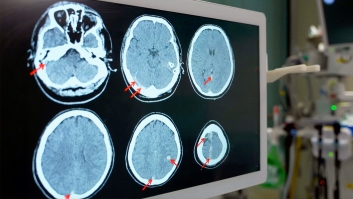

Covid-19 hat gezeigt, wie unberechenbar und global Krankheiten zuschlagen können. Doch die nächste Pandemie ist nur eine Frage der Zeit. Gesundheitsexperten betonen die Notwendigkeit verstärkter Überwachung und internationaler Kooperation, um solche Bedrohungen zu bewältigen. Vorbereitung und Frühwarnsysteme sind entscheidend, um die Sicherheit und Gesundheit der Weltbevölkerung zu schützen.

Tödliche Naturgewalten

Pandemien

Covid-19 hat gezeigt, wie unberechenbar und global Krankheiten zuschlagen können. Doch die nächste Pandemie ist nur eine Frage der Zeit. Gesundheitsexperten betonen die Notwendigkeit verstärkter Überwachung und internationaler Kooperation, um solche Bedrohungen zu bewältigen. Vorbereitung und Frühwarnsysteme sind entscheidend, um die Sicherheit und Gesundheit der Weltbevölkerung zu schützen.

Auf Abruf bei:

Covid-19 hat gezeigt, wie unberechenbar und global Krankheiten zuschlagen können. Doch die nächste Pandemie ist nur eine Frage der Zeit. Gesundheitsexperten betonen die Notwendigkeit verstärkter Überwachung und internationaler Kooperation, um solche Bedrohungen zu bewältigen. Vorbereitung und Frühwarnsysteme sind entscheidend, um die Sicherheit und Gesundheit der Weltbevölkerung zu schützen.

Tödliche Naturgewalten

Pandemien

Covid-19 hat gezeigt, wie unberechenbar und global Krankheiten zuschlagen können. Doch die nächste Pandemie ist nur eine Frage der Zeit. Gesundheitsexperten betonen die Notwendigkeit verstärkter Überwachung und internationaler Kooperation, um solche Bedrohungen zu bewältigen. Vorbereitung und Frühwarnsysteme sind entscheidend, um die Sicherheit und Gesundheit der Weltbevölkerung zu schützen.